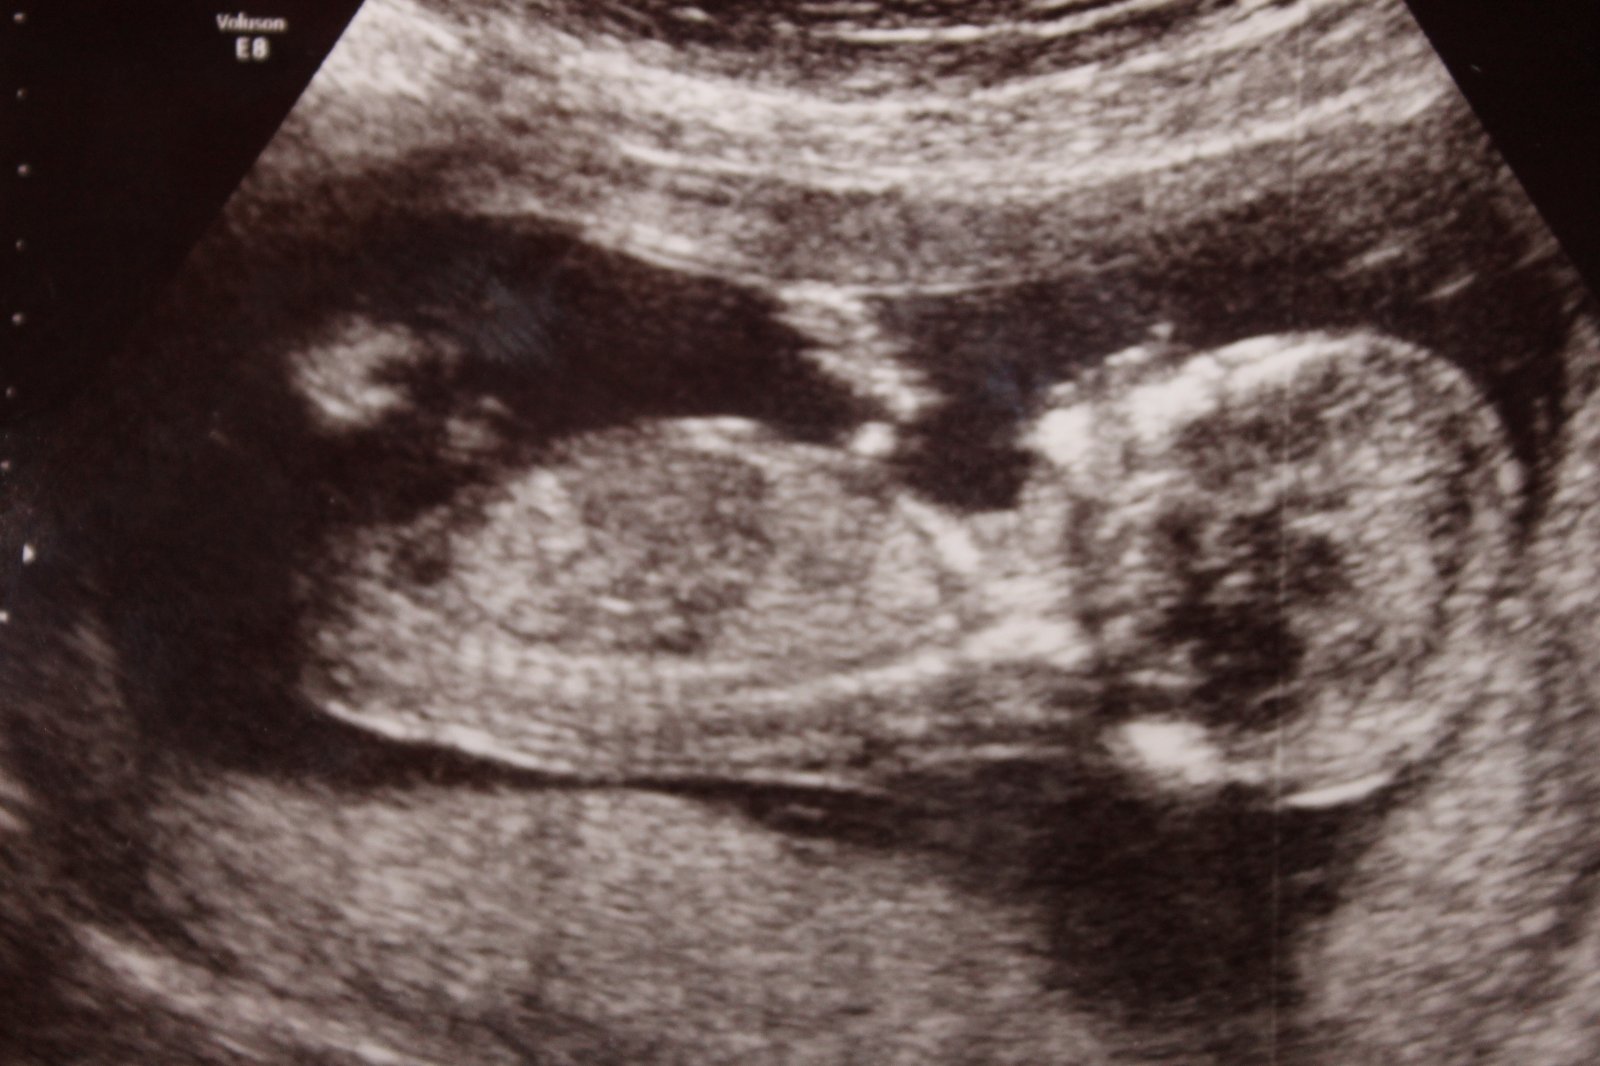

nám na NT screeningu ve 13tt řekl dr., že podle sklonu pohlavního výběžku si je téměř jistý, že je to holčička (u holčiček výběžek směřuje kolmo dolů, u kluků šikmo dopředu). Brala jsem to s rezervou a taky trochu skepticky, měla jsem totiž pocit, že je to kluk. Ve 21tt se holčička potvrdila. Už jsem slyšela víckrát, že dr. poznal pohlaví takto brzo, takže tomu začínám věřit. Myslím, že když je zkušený dr. a má kvalitní UTZ, tak se pohlaví kolem 13tt poznat dá.

Ahoj, já jsem 13+1tt, Na Veveří v Brně mi na screeningu potvrdili na 90% kluka. Pozná se to prý podle pohlavního hrbolku - podle Dr. klukům vrcholek hrbolku míří víc nahoru k bříšku a holky ho mají protáhlejší směrem dolů k nožkám...Uvidíme, co nám potvrdí příště 🙂 ale já věřila, že je to bude kluk už od oné noci 😀 poprosila jsem o něj 😀 a to překvápko, když mi to potvrdili 😀 MUDr. Doubková umí vše krásně vysvětlit, je precizní a velmi příjemná... 😉